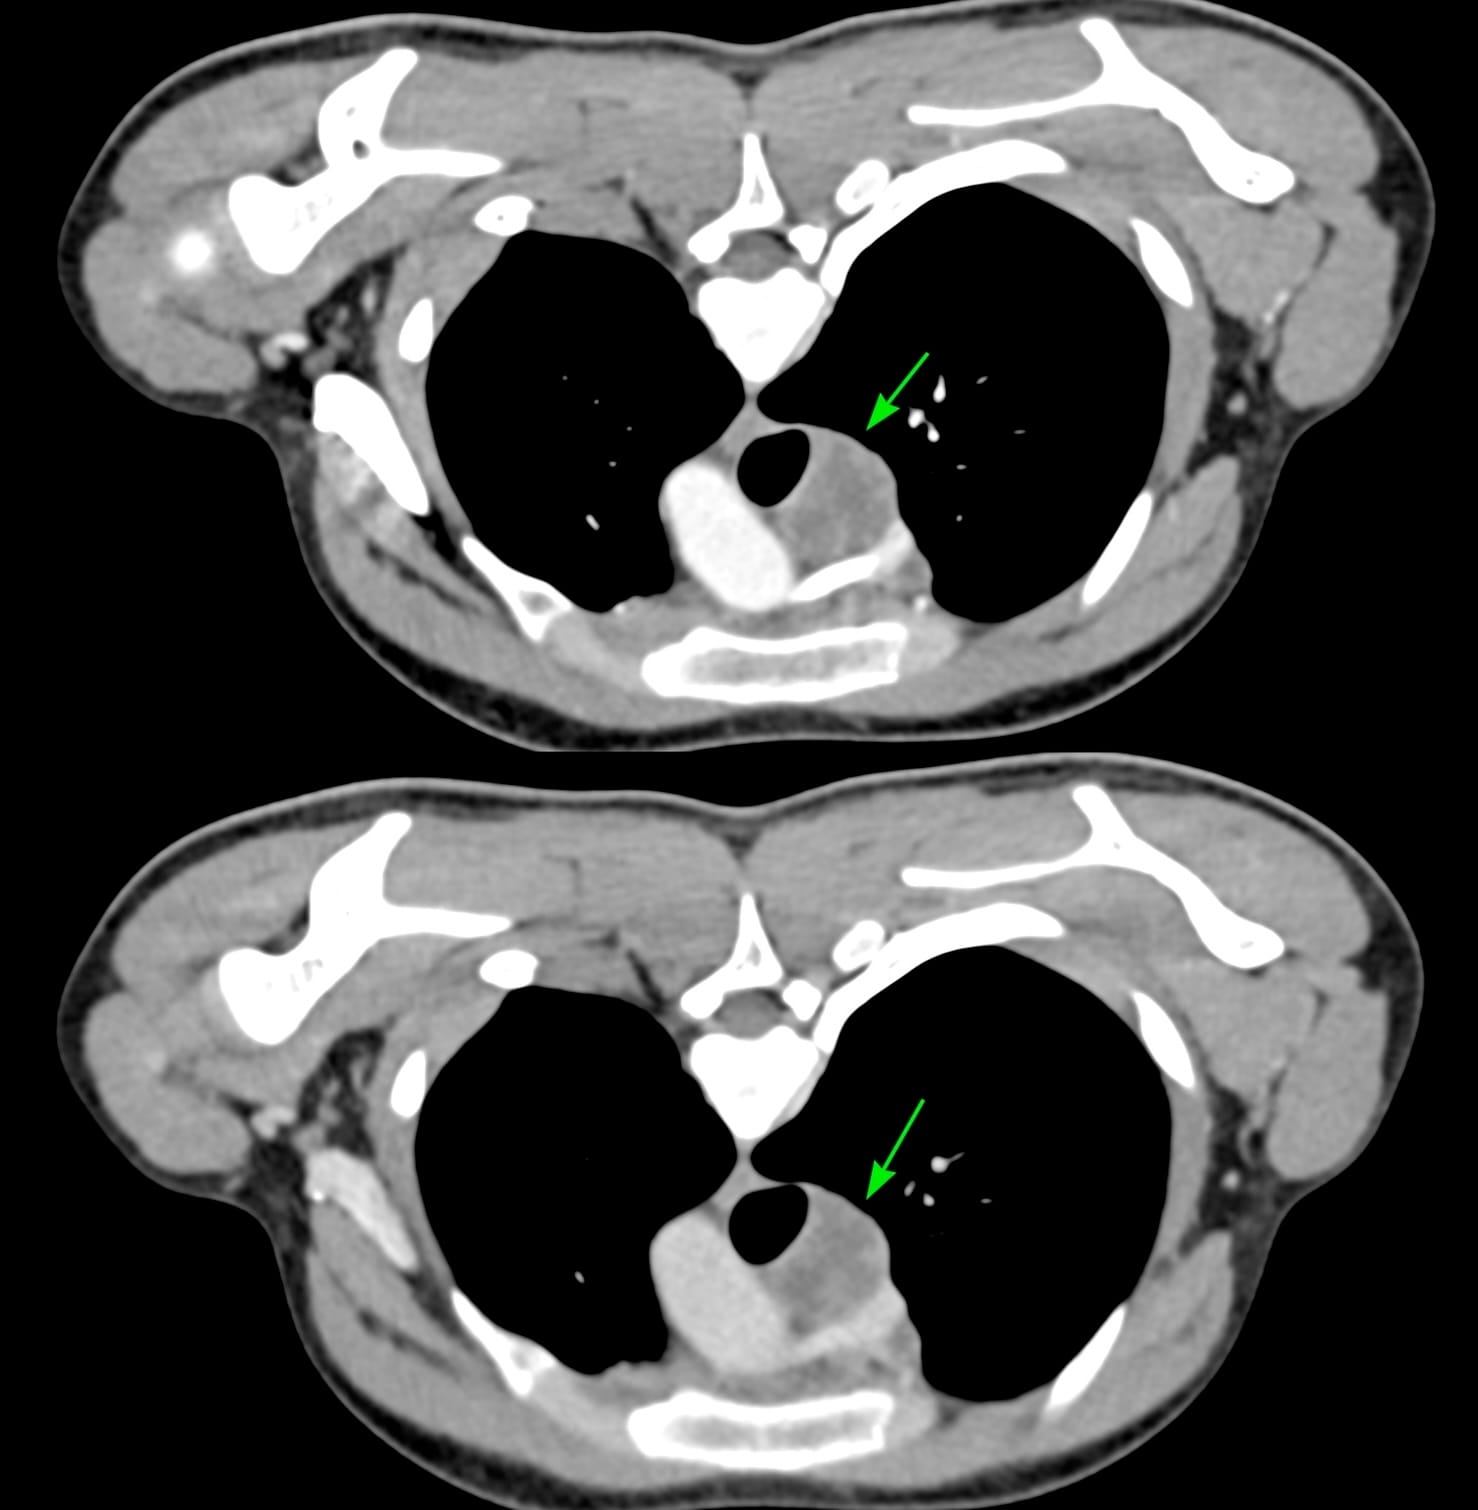

17-years old with fever had a PET/CT that showed a necrotic right paratracheal node - 4R - and was referred for a CT guided biopsy.

Arterial and venous phase studies in the prone position just prior to the biopsy showed the necrotic node well.

While an extrapleural biopsy with hydrodissection is what I usually do, in this case, the lung was extending more medially and a transparenchymal route made more sense.